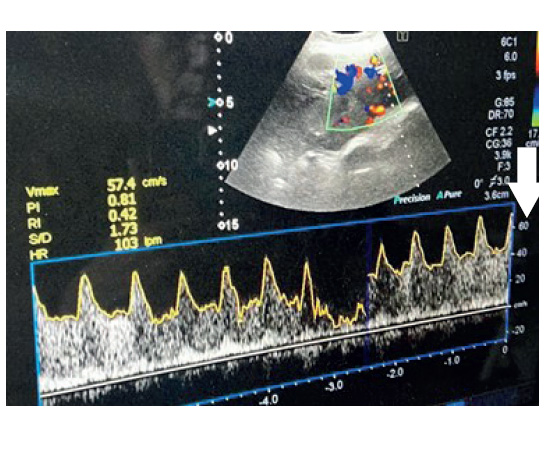

Figura 5 Medición de la flujometría Doppler.

En la valoración ecográfica (tabla 2), la pérdida de la zona clara de la inserción placentaria para pacientes con sospecha de acretismo fue de 41,7%, había lagunas placentarias ovaladas no circulares de bordes irregulares en 75,0%, interrupción de la pared vesical en 50,0%, heterogeneidad e hiperecogenicidad placentaria en 66,7%, placa corial de aspecto despulido, hiperecogénica e irregular en 75%, hipervascularización uterovesical en 58,3%, hipervascularización subplacentaria en 50,0%, vasos nutricionales y lagunas placentarias hipervascularizadas en 66,7%, hipervasculatura intraplacentaria en 50%, y velocidad máxima de flujo de 52,3 cm/seg.

El análisis estadístico mostró que la pérdida de la zona clara, las lagunas placentarias ovaladas no circulares de bordes irregulares, la interrupción de la pared vesical, la hiperecogenicidad y heterogeneidad placentaria, la placa corial de aspecto despulido, hiperecogénica e irregular, la hipervascularización útero vesical así como la hipervascularización subplacentaria, vasos nutricionales e hipervascularización intraplacentaria presentaron relación estadísticamente significativa con el acretismo placentario (p<0,05). Y laflujometría representada por la velocidad máxima encontrada en el estudio Doppler con barrido de toda la placenta fue 52,3 para acretismo frente a 26,0 en placentas previas sin signos de acretismo, diferencia que fue estadísticamente significativa (p<0,05).

En la tabla 3 se muestra la regresión de Cox para el riesgo de acretismo y la supervivencia de las pacientes, donde se evidencia que las pacientes con una velocidad de hasta 53,4 cm/seg tuvieron un riesgo de acretismo de 1,0 con probabilidad de sobrevida de 33,3%. Sin embargo, las mujeres con una velocidad de flujo Doppler de 54,8 cm/seg presentaron incremento del riesgo de acretismo a 2,4 y la probabilidad de sobrevivencia disminuyó a 8,3%.

En la figura 1 se observa la regresión de Cox según la velocidad de flujo en relación con la supervivencia, en la que se ve que con una velocidad de flujo Doppler entre 40 y 50, el riesgo de acretismo es aproximadamente 1. Pero, si aumenta la velocidad de flujo Doppler a más de 50, la sobrevida disminuye (a más velocidad, la probabilidad de sobrevivir disminuye y el riesgo de acretismo aumenta).

La evidencia de los resultados muestra que, además de las variables utilizadas en el European Working Group on Abnormally Invasive Placenta (EW-AIP) 7), clasificación que tiene aproximadamente ocho años, las variables agregadas en nuestro estudio fueron tres: hiperecogenicidad placentaria y heterogénea, placa corial de aspecto de despulido e hiperecogénica irregular, y la velocidad máxima de flujo (cm/seg), que denotan una diferencia estadística significativa como aporte en el diagnóstico de acretismo. Por otro lado, se ha determinado el punto crítico de la flujometría placentaria como factor de riesgo de acretismo y pronóstico de sobrevida de las pacientes 18,19).

La determinación ecográfica de la hiperecogenicidad placentaria heterogénea, placa corial hiperecogénica irregular (aspecto despulido) y la velocidad máxima del flujo Doppler (cm/seg) representan parámetros útiles de aporte al diagnóstico de acretismo placentario.